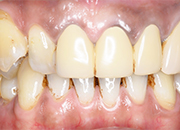

症例2

患者さんは60代男性 以前入れた保険の歯が色が変わって歯ぐきもやせたので白くしたいと希望術後

きれいに入って「こんなに保険の歯と違うのですか、入れて良かった」と喜んでおられました。

1本80000円(税別)

術前

術後